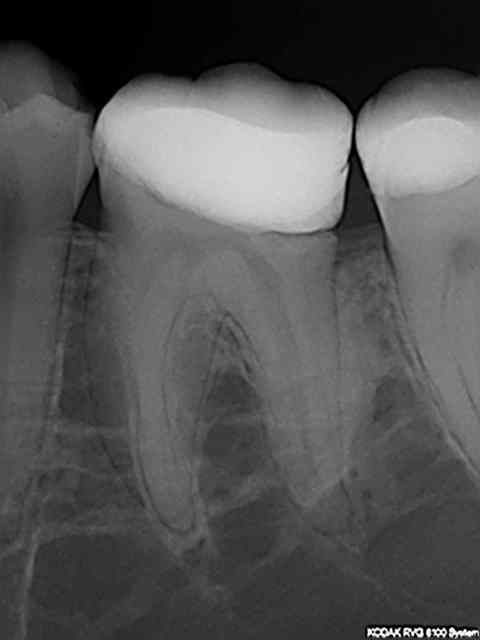

J'ai fais un cas, molaire, ça va bien.

C'est pas une pulpec, c'est une endo, une bio vous dites ?

Dent partiellement nécrosée, carie pulpaire au distal.